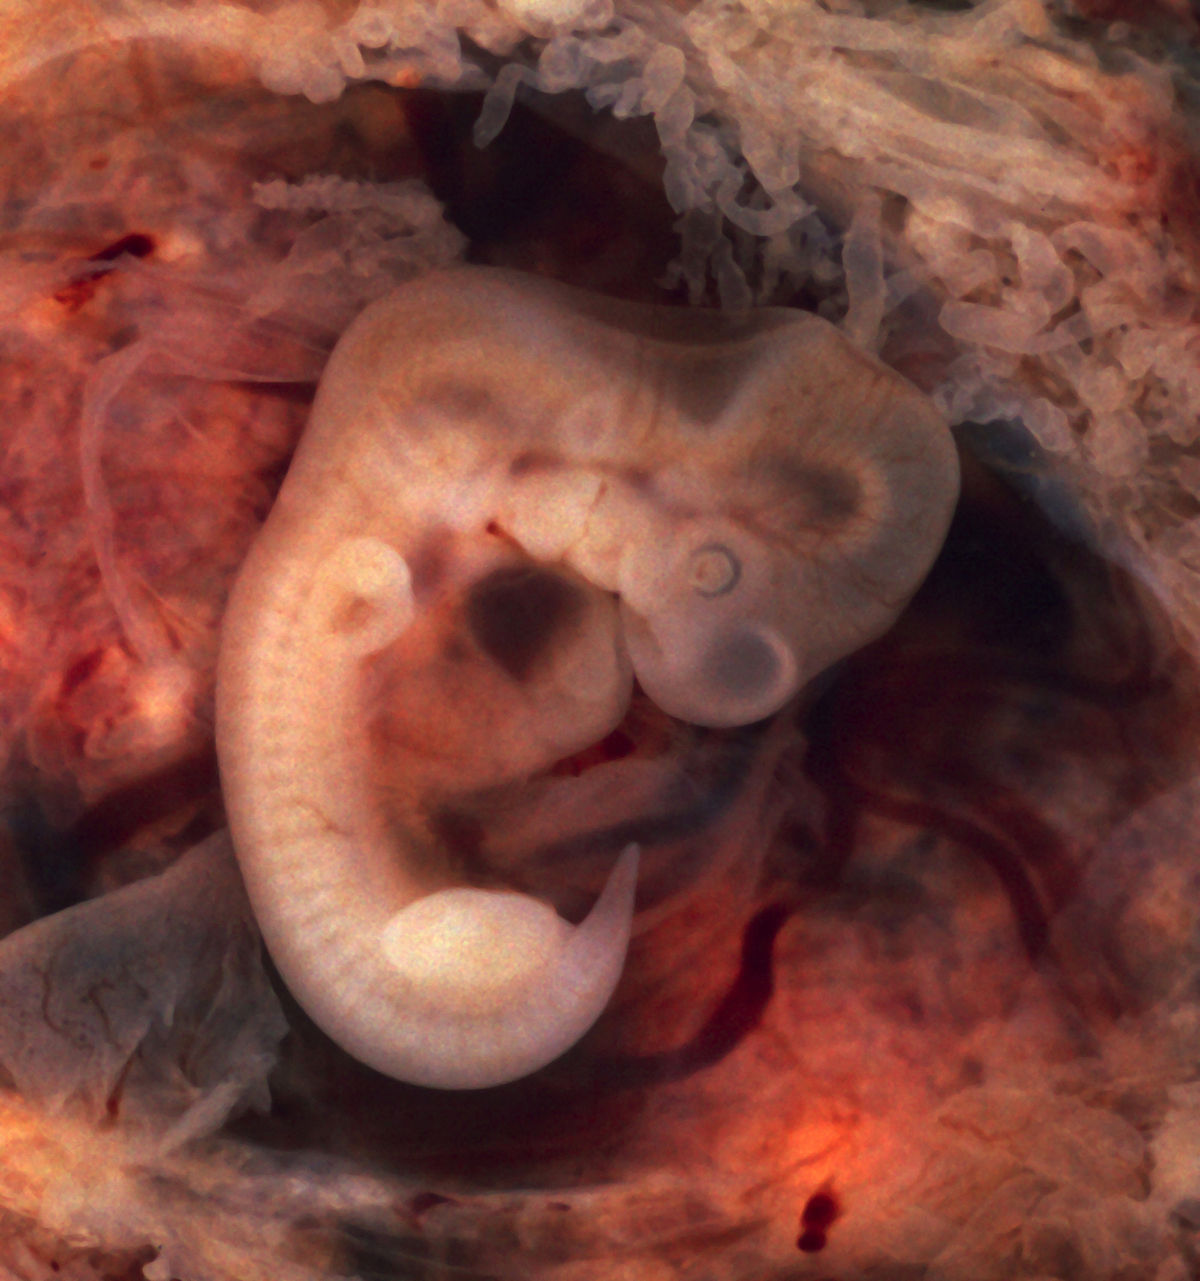

Удивительные фотографии эмбриона на 8 неделе беременности